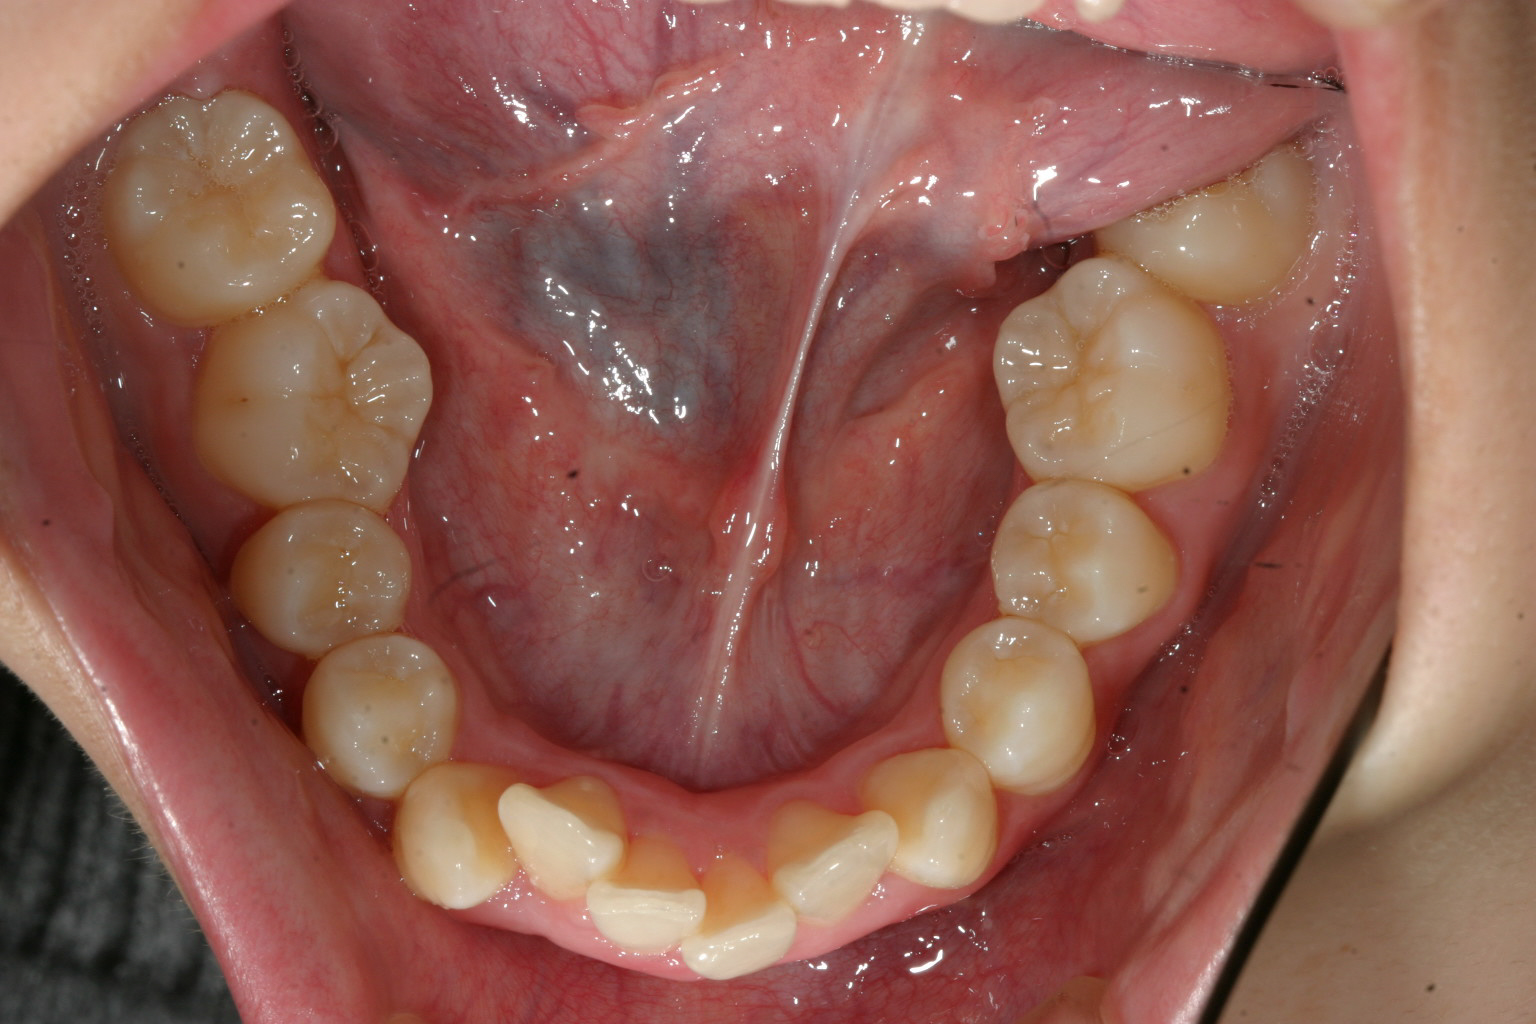

上顎前歯が飛び出しています。

下顎もかなり乱れています。